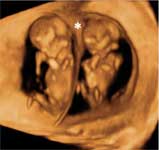

Semana 16 del embarazo gemelar monocorial

En la semana 16 del embarazo monocorial de gemelos toca hacerte una ecografía. Medirán a ambos bebés, confirmarán su latido cardíaco y estudiarán sus principales órganos y estructuras fetales.

Te realizarán una ecografía por vía abdominal. Lo primero que se constatará en la imagen ecográfica será el latido cardiaco de ambos fetos. Posteriormente se medirá el diámetro biparietal (cabeza), la circunferencia abdominal (abdomen) y la longitud del fémur (pierna). Se hará un estudio de la anatomía de ambos fetos. Esta ecografía debe realizarse por ecografistas cualificados y con aparatos de alta resolución.

La ecografía es la reina de las pruebas diagnósticas, pero hay muchas otras que se pueden realizar a las embarazadas. La ecografía es un arma especialmente importante en la gestación gemelar, para su diagnóstico y para controlar los riesgos asociados a este tipo de gestación. Lo primero que observará el ecografista es la membrana de separación entre los hermanos, si es que existe, y se cerciorará del número de placentas: una, dos. Pero hablamos también de pruebas invasivas como la amniocentesis y cordoncentesis o biopsia corial.